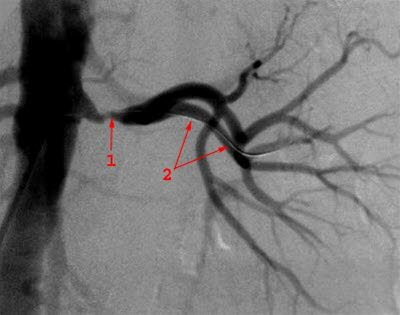

Nyrearteriestenose, kontrastrøntgen.Ved nyrearteriestenose er det en forsnevring (stenose) av en eller begge nyrearteriene. Det er hovedsakelig to årsaker til en slik forsnevring:

I tillegg finnes det ulike metoder for å påvise og kartlegge omfanget av forsnevringen. Blant de mest brukte alternativene er ultralyd eller isotopundersøkelse. Eventuelt benyttes CT eller MR. For endelig bekreftelse benyttes angiografi, som er en røntgenundersøkelse der nyrearteriene fremstilles ved hjelp av kontrastvæske.